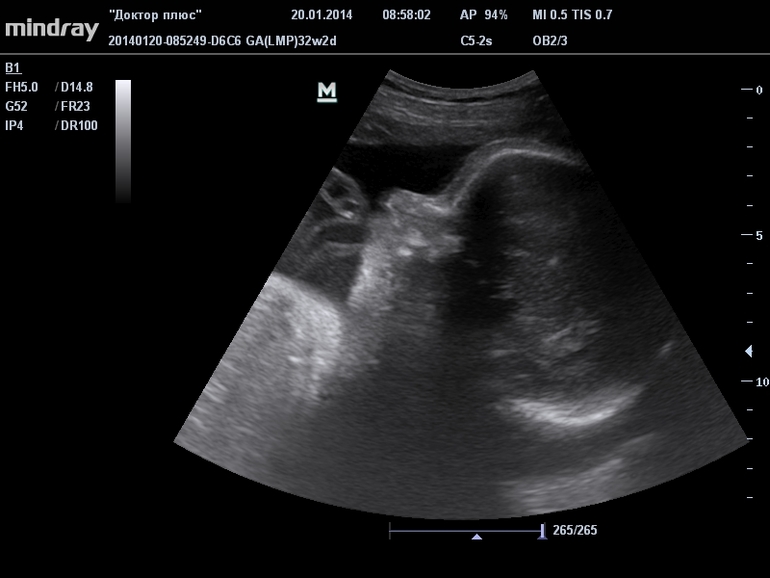

УЗИ 32 недели

УЗИ, КТГ, доплерСпешу поделиться результатами третьего узи! Как всегда ужасно волновалась перед этим наверно целую неделю, но все в норме у нас) Сынок крупненький вырос. По месячным у нас срок 32 недели 2 дня, а по размерам головки, плеч и ножек на 2 недели больше. В итоге в заключении написали 33 недели 3 дня. Может и родится пораньше?)))

Выдали нам штук 6 фоток, голова, лицо, причиндалы, ножку и еще какие-то. Вот выложу одну, где получше видно.